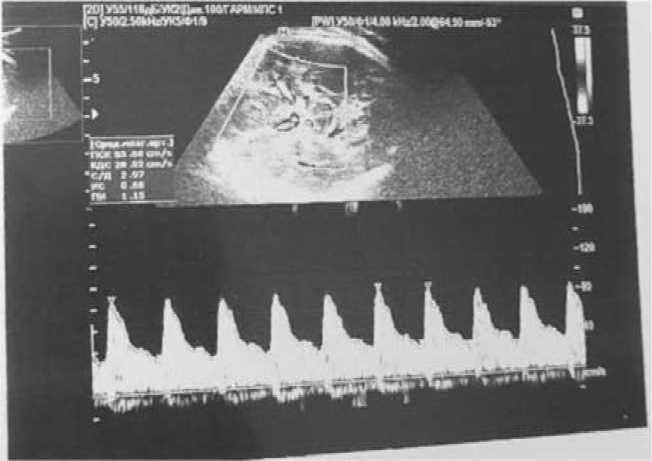

При повторной телемедицинской консультации (20 марта 2023 г.) на 36-й неделе беременности была отмечена положительная динамика при ультразвуковом обследовании (проводимом 20 марта 2023 г., рис. 5) – уменьшение водянки плода, ультразвуковых признаков анемии не было выявлено (что связано со снижением числа копий антител к парвовирусу В-19 (количество копий на момент проведения телемедицинской консультации – 0,70), выявляемый при антенатальном ультразвуковом исследовании ВПС не является критическим. Даны рекомендации по продолжению наблюдения и ведения пациентки в условиях стационара, продолжению оценки СМА плода, контроля допплерометрией и КТГ, ведению дневника шевелений плода. Сроки и способ родоразрешения провести согласно акушерским показаниям, после рождения проведение ЭхоКГ.

Рис. 5. Фотофиксация изображений АУО плода на 36-й неделе беременности